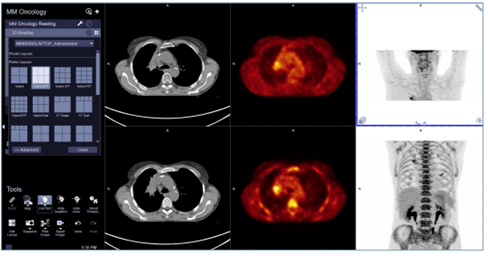

在放療療效評估過程中,為觀察病灶的變化,需要醫師進行多個時間點圖像的比較,因此需要圖像之間的同軸配準。傳統的配準方法是逐像素進行的,然而當兩次檢查的視野、患者姿勢(如:手臂舉起VS手臂放下)或檢查床設置(如:厚床墊VS薄床墊)發生變化時,傳統算法會失效,錯誤的配準可能導致病灶消失的假象。

西門子ALPHA人工智能引擎基于專利的器官識別技術進行解剖學配準,使醫師更便捷的對比不同檢查的數據。該技術在每幅圖像中探測多達28個解剖學標識,基于解剖一致性檢查進行過濾,并利用重疊標識對不同時間點的圖像進行配準。由于ALPHA配準是以解剖結構識別為基礎的,就像人工進行圖像配準一樣,而不是低水平的像素匹配,不受前述所有變化的影響,實現了不同時間點PET/CT圖像的精確配準。

ALPHA配準可對多時間點的檢查圖像進行匹配,即使它們有不同的FOV